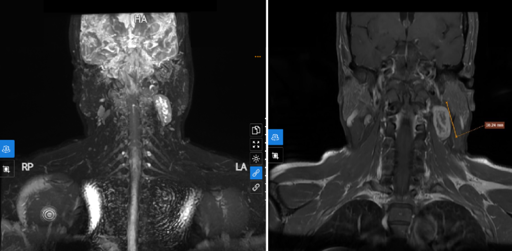

Nếu thấy cần thiết, bác sĩ sẽ chỉ định phẫu thuật. Những trường hợp phải can thiệp bằng phương pháp điều trị này chủ yếu là để loại trừ nguyên nhân gây liệt dây thần kinh số 7 như áp xe não, u não, có khối máu tụ, viêm tai xương chũm,...